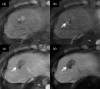

MRI is widely used in clinical practice for detecting liver diseases. Since the introduction of gadoxetic acid, MRI has become the most effective modality for the detection and characterization of focal liver lesions. According to previous meta-analyses, the area under the receiver operating characteristic curve (AUROC) was 0.97-0.99 for the diagnosis of small hepatocellular carcinoma (≥ 2 cm) by gadoxetic-acid-enhanced MRI. Moreover, the AUROC for the diagnosis of colorectal liver metastases was significantly high (0.98). Despite gadoxetic acid's drawbacks, its clinical utility outweighs them, making it the contrast agent of choice in routine liver MRIs. Moreover, clinically, liver MRI has become more prevalent for a quantitative assessment. Liver fibrosis can be evaluated using MR elastography; whereas, hepatic steatosis and iron overload can be evaluated using proton density fat fraction, with high accuracy and reproducibility. This article reviewed the usefulness of liver MRI, which can be a comprehensive imaging modality in clinical practice.